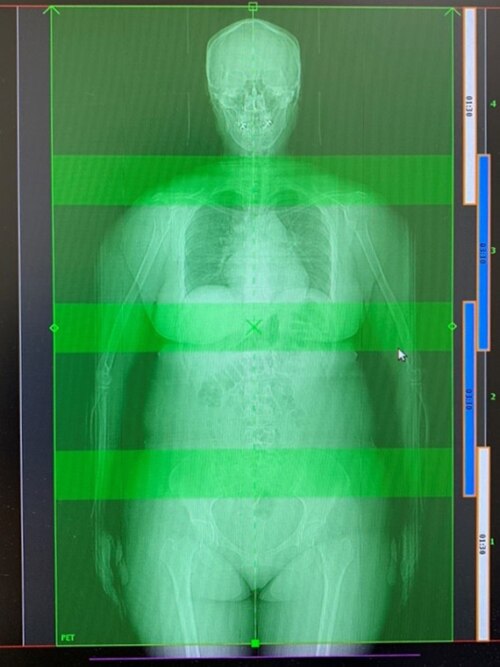

Omni Legend 32は、1Bedの体軸方向撮影範囲は32cmと長く、オーバーラップ25%とすると約102cmの範囲が4Bedで撮影できるため、ほとんどの受診者を頭部から骨盤部までカバーすることができます。(図3)

図3. 実際のプロトコル設定画面の一例

図3 は163.4cm 女性の撮影時プロトコル設定画面です。4Bed オーバーラップ25%で頭部から骨盤部まで余裕を持って撮影範囲に含めることが出来ます。

1Bedあたりの撮影時間を90秒とし体幹部の呼吸性移動のある部分には、Advanced Motion Free(AMF)を適用させています。AMF30~80%の50%のデータを使用するため、体幹部2Bedは180秒撮影としています。総撮影時間は9分となります。